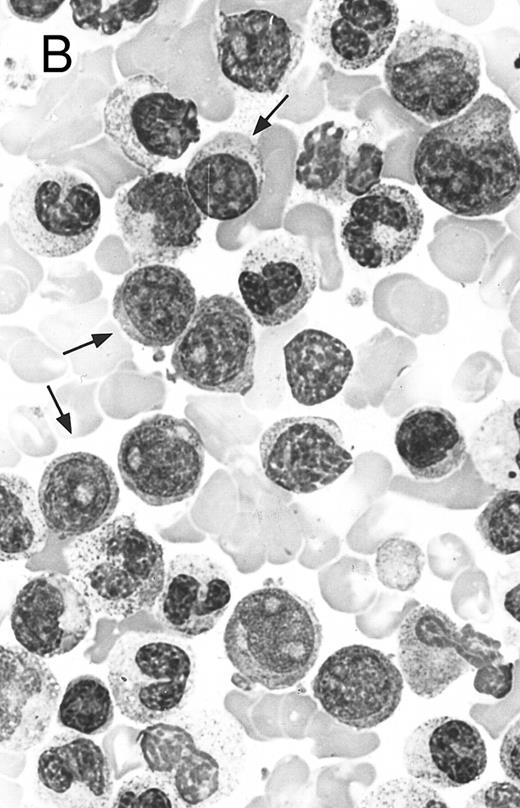

Two different cases of aggressive NK cell leukemia/lymphoma. (A) Peripheral blood shows increased large granular lymphocytes, most of which are mature-looking (case no. 36). The cell in the center is slightly less mature. (B) Buffy coat smear shows immature large granular lymphocytes with more open chromatin and distinct nucleoli (arrows) (case no. 37). Myeloid cells are seen in the background.

There were very few to numerous granular lymphocytes in the peripheral blood. Some of the granular lymphocytes were indistinguishable from normal large granular lymphocytes, with round nuclei, dense chromatin, and pale cytoplasm with fine azurophilic granules (Fig 5A). Some granular lymphocytes had larger nuclei with more open chromatin and distinct nucleoli (Fig 5B); occasional nuclei could show indentations. The azurophilic granules were sometimes large and coarse. There were also circulating normoblasts and immature myeloid cells. Marrow involvement ranged from subtle to extensive. In histologic sections, irrespective of site, there was a monotonous infiltrate of medium-sized cells with round nuclei and fairly condensed chromatin (Fig 6). Karyorrhexis was prominent. The infiltrate was diffuse, interstitial, or angiocentric.